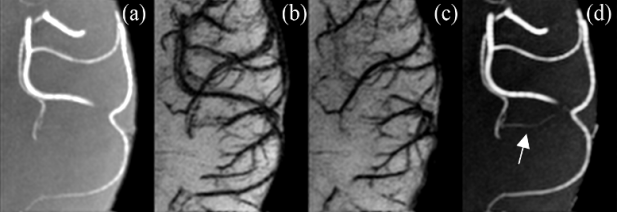

心脑血管疾病的临床诊断中,除血管的解剖结构外,其功能参数对心脑血管疾病的诊断至关重要,而这些参数无法通过对影像的直接观察获取。目前,临床应用中尚无法满足对于组织及器官功能参数深入的定量分析处理,不能对疾病的诊断和治疗提供更为准确、深入的支持。

CT和MRI影像中的定量分析

该方向针对心脑血管疾病专病队列,重点解决多级血管结构提取与定量分析,心脑结构形态学的分割与定量描述,血管结构中血流动力学参数测定,脑局部区域氧代谢指标测量,血管渗透性的定量表征参数测量,氧饱和度测量与关联分析,脑局部区域氧代谢指标测量以及缺血半暗带定位及脑出血转化预测分析等技术问题,并基于上述定量分析参数构建心脑血管疾病的精准医学知识库。在此基础上,实现组织的纤维、脂质、钙化、坏死成份、炎性成份等的定性分辨以及缺血性脑卒中患者发生脑出血转化的可能性预测等重要高端医疗影像临床辅助应用。